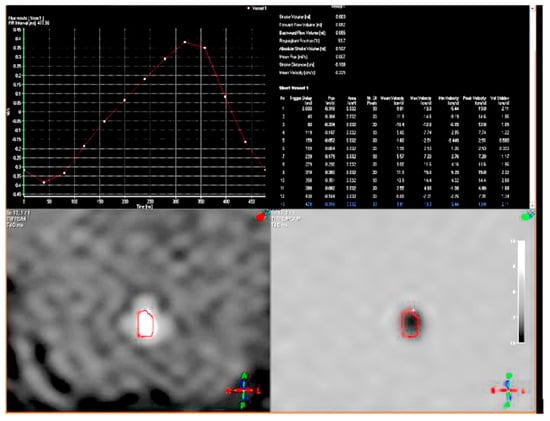

| Our patient | 46, XX, der(8)del(8)(p23.1)invdup(p12p23.1) | + | Developmental and speech delay. No meaningful sentences. Hypotonia. Hypothyroidism. Prominent forehead, arched eyebrow, thin nose with rounded tip and anteverse nostrils, flat filter, thin down-turned lips, slight micrognathia, low-set posteriorly rotated ears. Single palmar crease on the right hand and bilateral IV-V fingers clinodactyly. Hypertrichosis, previous sacrococcygeal fistula sign. Extra-rotation of the lower limbs, varus position of both the knees, flat feet. Bilateral cutaneous dimples on both elbows and knees, shield chest, inverted nipples, winged shoulder blades. Emotiveness, impulsiveness, decreased attention span. Dilatation of lateral ventricles, pineal gland’s small ectasia, moderate cystic cisterna magna’s ectasia, retrocerebellar cystic ectasia. Global chorio-retinic dystrophia, pale papilla with clear boundaries, peri-papillar pigmentary ring. Sialorrhea and extravelic palatin tonsils, ogival palate, type C tympanogram with absent stapedial reflex on the left. |